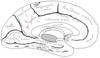

Key gyri on medial view of frontal lobe

Superior frontal gyrus

Paracentral lobule

Cingulate gyrus

Key sulci on medial surface of frontal lobe

Cingulate sulcus